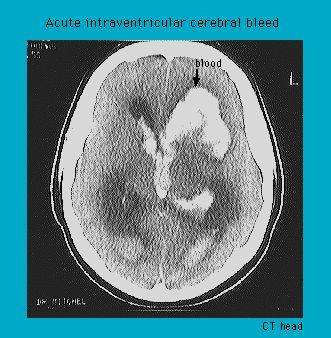

Tomodensitométrie montrant une hémorragie intraventriculaire